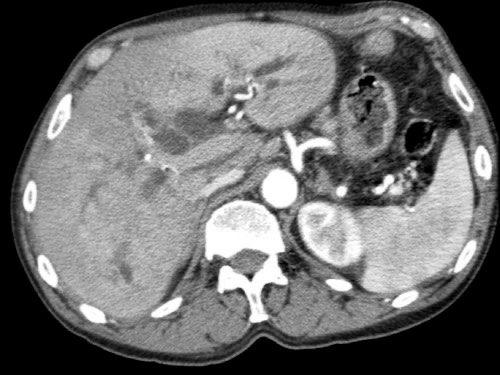

Dấu hiệu giọt nước mắt. Khối u lớn ở thân tụy, tiếp xúc 90 – 180 độ với SMV, đồng thời gây biến dạng SMV thành hình giọt nước mắt, rất nghi ngờ xâm lấn.

- Dấu hiệu giọt nước mắt (Teardrop sign)

Chỉ sự thay đổi hình dạng của tĩnh mạch cửa (PV) hoặc SMV từ hình bầu dục hoặc tròn sang hình giọt nước mắt. Điều này có thể do khối u bao quanh hoặc do xơ hóa lân cận kéo căng mạch máu. - Bất thường bờ viền mạch máu